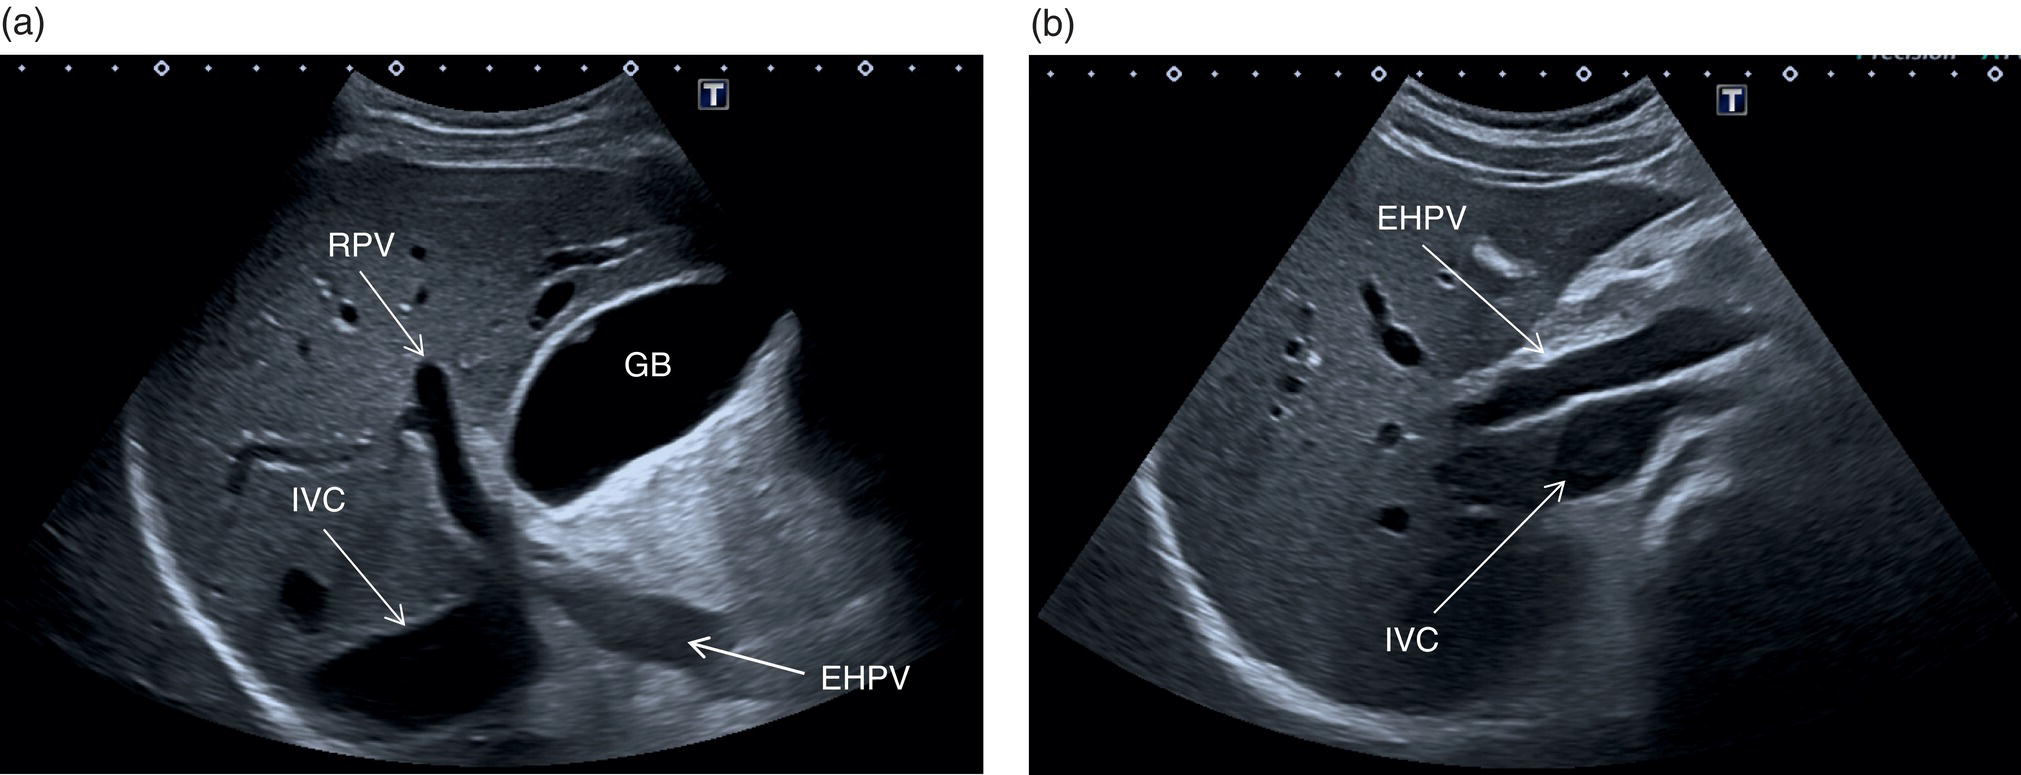

Portal Vein, Hepatic Artery, and Hepatic Veins

The PV is best assessed in the intercostal position, typically when scanning through the right liver segments. When scanning intercostally be sure to visualise the hepatic hilum and the main PV (the main trunk will appear as the more posterior structure) (Figure 3.32a). Alternatively the main PV can be visualised maintaining a subcostal oblique approach (Figure 3.32b). In order to visualise the origin of the main extrahepatic PV, start by searching the splenic vein with a transverse subcostal epigastric view. The splenic vein will be seen lying below the pancreas and above the superior mesenteric artery in its transverse section (Figure 3.33a). Once the splenic vein is visualised, slowly turn the probe clockwise approximately 90° in order to visualise the superior mesenteric vein (Figure 3.33b). Next turn the probe anticlockwise by 45°, maintaining an oblique subcostal position. By doing so the confluence of the splenic vein and superior mesenteric vein will be seen forming the extrahepatic PV entering the liver (Figure 3.33c) (Video 3.11). It is important to remember that there may be subjective variability in the visualisation of hepatic structures, especially of the vessels, according to the angle of insonation. Therefore, it is advised to follow the mentioned landmarks moving slowly, since small movements of the probe can lead to considerable changes in ultrasound imaging. ![]()

The PV is formed by the confluence of the superior mesenteric vein and the splenic vein, draining the blood of the whole digestive system and spleen (Figure 3.11). Under physiological conditions the portal venous system delivers 75% of the total hepatic inflow, whereas the hepatic artery (HA) is responsible for the remaining 25%. It is important to keep in mind the physiology and pathophysiology of the hepatic blood inflow, since during the progression of liver disease, especially when cirrhosis and portal hypertension develop, the portal venous inflow is reduced while the arterial hepatic inflow is increased (See Chapter 8). The PV can be recognised on ultrasound as a tubular structure with a variable normal calibre of approximately 8–12.5 mm, with thick echogenic walls that enters the liver together with the HA at the level of the hepatic hilum. It is followed by the HA and the biliary system in its whole intrahepatic course and for a short portion in its extrahepatic tract at the level of the porta hepatis, where it is contained within the hepatoduodenal ligament. Upon entering the liver, the PV and HA divide into the left and right branches, with further divisions providing the blood supply to each of the eight main liver segments (Figure 3.12). At the periphery of the liver lobules the arterial and venous blood mix and enter the sinusoids, terminating finally in the central veins that converge to form the right (RHV), middle (MHV), and left hepatic veins (LHV) that finally drain into the IVC (Figure 3.13). It is of note that the caudate lobe is drained independently by a main or multiple small pericaval veins. Its independent venous drainage system is the reason why the caudate lobe typically hypertrophies in advanced chronic liver disease. In Budd–Chiari syndrome, this compensatory mechanism is even more pronounced, since while the main three hepatic veins are obstructed, the pericaval ones often remain patent, leading to an abnormally hypertrophied caudate lobe (See Chapter 11).